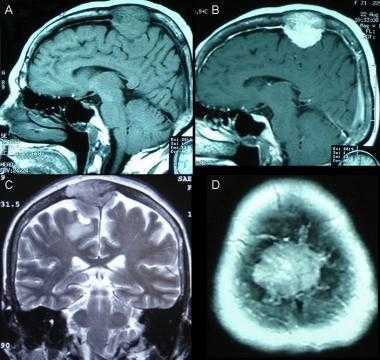

Фалькс-менингиома на МРТ.

А: на Т1-взвешенном МР-изображении отмечается солидное образование, характеризующееся изоинтенсивностью по отношению к твердой мозговой оболочке, инвазией в кость и сдавлением теменных зон коры.

В: На Т1-взвешенном МР-изображении с контрастным усилением видна частично контрастируемая опухоль.

С: На корональном Т2-взвешенном изображении видно изоинтенсивное образование, что соответствует плотной ткани. Такая картина характерна для фибробластных менингиом.

D : На Т1-взвешенном МР-изображении с контрастным усилением визуализируется гиперинтенсивное образование внутри мозгового вещества кости.